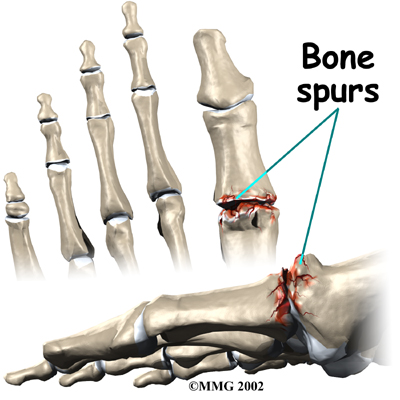

Bone spurs form around the joint as part of the degenerative process. The spurs, or bony outgrowths, may restrict the motion in the joint, especially the ability for the toe to bend upward as the body moves forward over the foot, such as when you are taking steps. The big toe becomes very stiff or immobile into this range of motion, hence the reference to rigidity in the name of this condition.

The degeneration at the toe joint causes two problems; pain and loss of motion in the MTP joint. Without the ability of the MTP to move enough to allow the foot to roll through a full step, walking can become painful and difficult. Pain is most noticeable during walking just before toe-off. Pain is increased when wearing shoes that have elevated heels. Bone spurs that develop with this condition can also put pressure on nearby nerves, causing numbness along the inside edge of the big toe.

In some cases bone spurs that form on the top of the joint can bump together when the big toe bends upward, or extends. This causes a problem when walking because the big toe needs to bend upward when the foot is behind the body, in order to take the next step. The constant irritation when the bone spurs bump together leads to pain and difficulty walking.